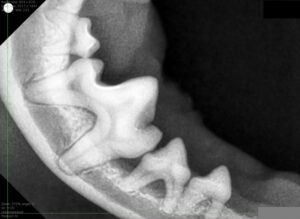

歯科用レントゲン検査です。専用センサーを口の中に入れて撮影するためわんちゃん・ねこちゃんでは麻酔をかけて行います。

今回この検査を行ったところ歯を支える骨(歯槽骨)が溶けている部分がありました。

このチワワさんは体重が2kg未満の子ですが、このまま顎の骨の喪失が続くと将来的に骨折するリスクもあります。

相談の上、今回はこの歯を抜歯することになりました。